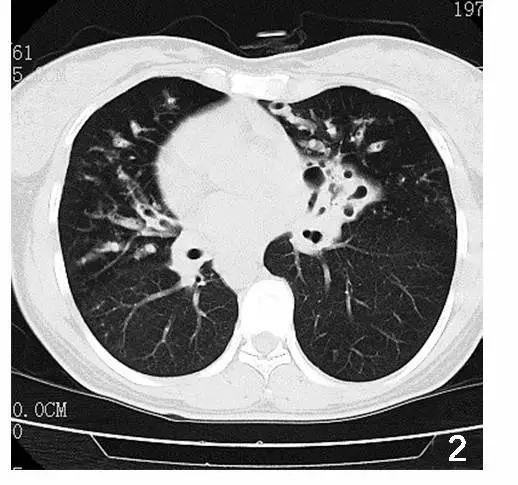

胸部 CT 结果报告显示「双肺纹理增多紊乱,双下叶支气管扩张,并树芽状结节」,同时进一步证实右位心,很明显看到心脏偏向右侧。心脏没有问题,心音和瓣膜音也很正常。

胸部 CT 平扫示:双下叶支气管扩张伴感染,右位心。(注:胸部 CT 横断面的图相当于是从脚看向头部,因此图上的左右是相反的;图源:参考资料 2,非本病例)